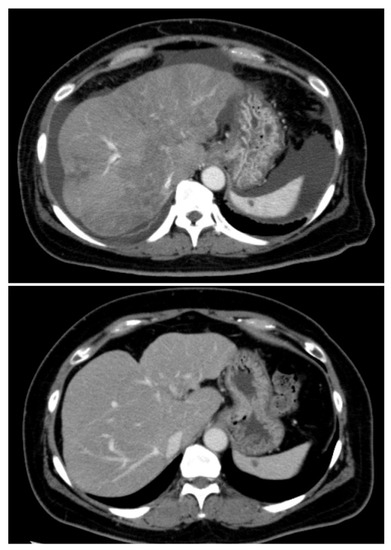

Successful Alectinib Treatment for Carcinoma of Unknown Primary with EML4-ALK Fusion Gene: A Case Report

2. Case Presentation